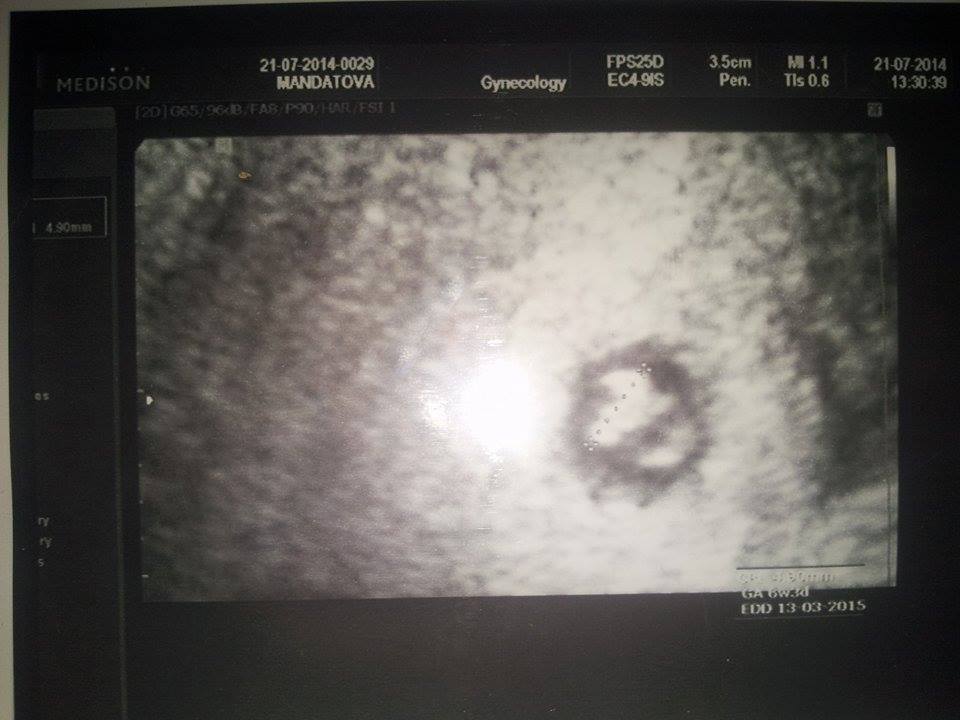

Dne 21.07.2014 jsem absolvovala plánovanou kontrolu.

Naštěstí mimi se vyvíjí jak má. Nyní jsem v 6+3tt (7tt) míry zatím 4,90mm srdíčko bylo pěkně vidět.

Nechala jsem si udělat 1. fotečku miminka.